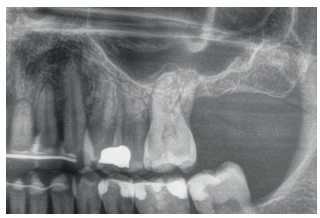

En las Figuras 2- 19 se muestra uno de los casos incluidos en el estudio.

pérdida ósea que presenta, además de una movilidad grado III.

imagen apical en la raíz distal. Se decide proceder a la extracción y regeneración con Endoret-PRGF además de la inserción de

un implante en la zona correspondiente al molar 27.

previamente con el anclaje del implante en la porción vestibular de la cresta ósea.

la oseointegración del implante 6 meses después de la cirugía. Se observa una ganancia ósea de 4 mm.